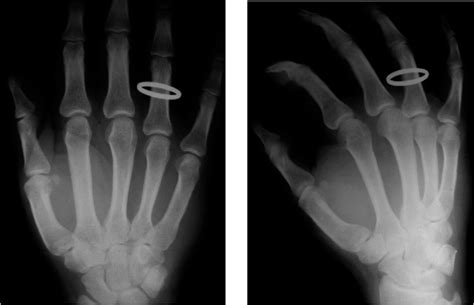

Because of their location, injuries to the sesamoid bones can be very difficult to treat. Sesamoid bones are located in the knees and feet. Sesamoid stress fractures are associated with localized tenderness over the involved sesamoid.

Seven months prior, she received a diagnosis of a medial sesamoid fracture. Journal of the american veterinary medical association. If surgery becomes necessary, several procedures are available to treat sesamoid problems. Sesamoids are found in several joints in the body. There are two methods for treating sesamoid problems, nonsurgical treatment and surgery. From injection therapy and orthotic care to surgical treatment options. A sesamoid is a bone embedded in a tendon. Sesamoid fractures occur as a result of trauma to a previous unipartite sesamoid bone. In other cases, if the sesamoids are fractured and does not heal correctly, removal of the sesamoids might be necessary. The most common cause of sesamoid fractures is from acute trauma to the foot, like if a person lands hard on their feet while running, jumping or falling. A sesamoid fracture that goes undiagnosed and untreated will invariably get worse. There can be inflammation of the tendons which are connected to the sesamoid (sesamoiditis) or there can be breakage of the sesamoid bone (sesamoid fracture). Seven months prior, she received a diagnosis of a medial sesamoid fracture. Pain will occur nearly immediately when a person fractures a sesamoid bone, but a person with sesamoiditis will experience pain gradually. Advanced treatments to rapidly heal sesamoid stress fractures. On some occasions, an acute fracture of unipartite sesamoid can be differentiated from a congenital bipartite. After the diagnosis from another physician, she did receive treatment, which included wearing a boot for five weeks.